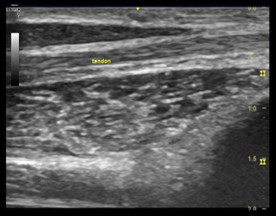

Se observa en la ecografía una red de líneas hiperecóicas finas y paralelas separadas por líneas hiperecóicas, ósea un patrón fibrilar. Los ecos lineales visibles dentro de los tendones dependen de las interfaces acústicas en los límites de los haces de colágeno y los tabiques del endotendineo. Mientras que el epitendineo suele verse como una línea reflexiva que rodea el tendón.

Imagen ecográfica 2.1 Eje longitudinal y transversal de los tendones del músculo flexor de los dedos.

Los tendones poseen gran anisotropía. Ósea los tendones tienen mayor  variabilidad de la ecogenicidad al modificar el ángulo de isonación. Además en comparación con los nervios el tendón posee menos ecos paralelos delgados y densamente empaquetados, es mas circular que oval  y mas móvil durante maniobras de flexión y extensión.